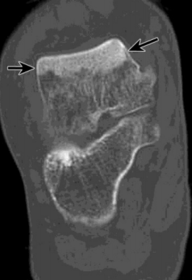

What is this? What is shown by A and B? | STJ coalition A = talar neck spurring B = Halo or 'C' sign |